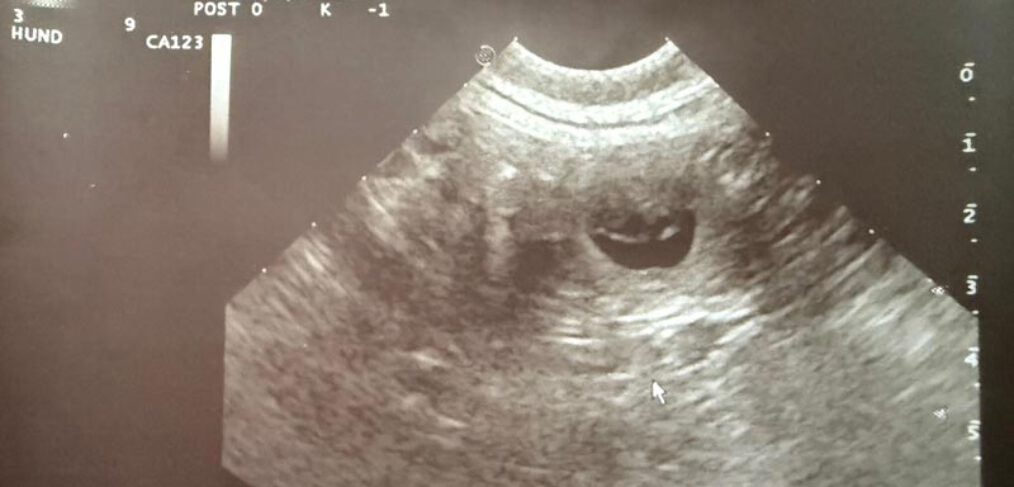

Kornay Hunting MATILDA wurde am 03.Mai von ALBIN Pondcastle of Alpine Girls gedeckt und die Trächtigkeit vom weltbesten Tierärzteteam PRAXIS KREUZBERGL bestätigt! Wir erwarten die Ankunft unseres V2 Wurfes Anfang Juli . Alle 18 Welpen von Gale und Prim sind bereits vergeben !